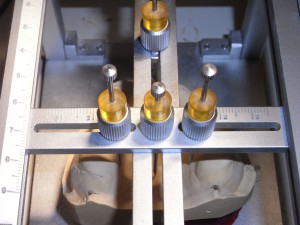

模型分析

模型分析